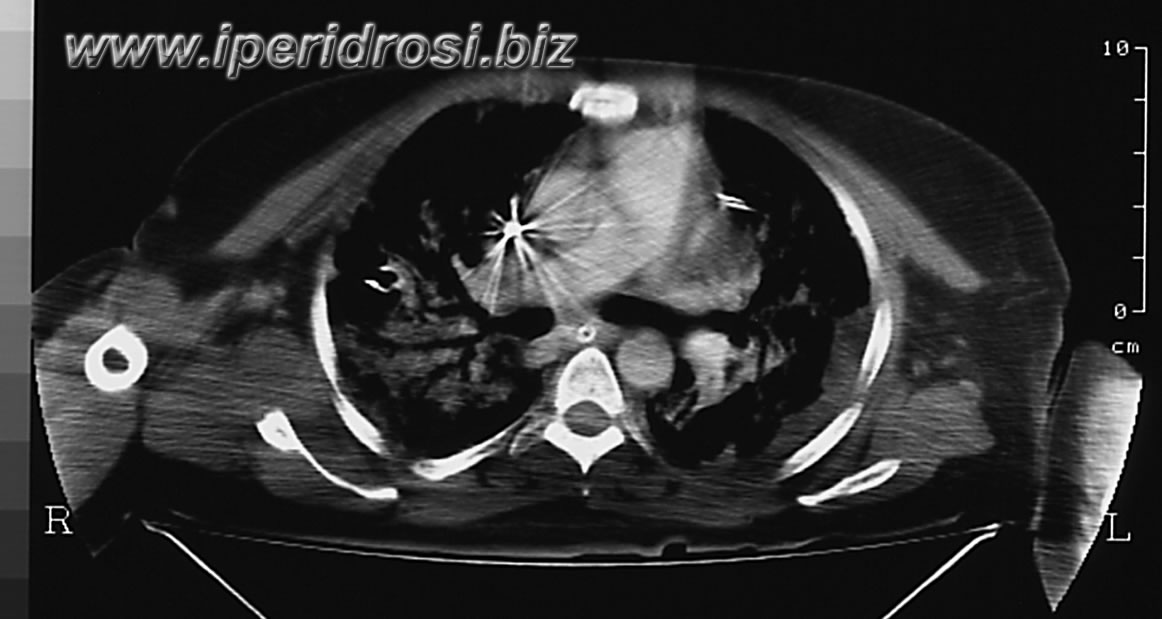

tac del giorno T 5

Al presente controllo si osserva regressione del versamento pleurico sinistro e comparsa di addensamenti interstizio alveolari diffusamente confluenti da ambo i lati. Residua piccola falda liquida peri e sotto epatica. Non falde di gas libero